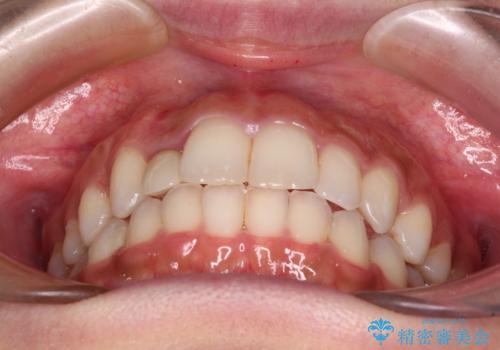

抜けてしまうと言われた前歯 インビザラインによる矯正治療

- 上下前歯のデコボコを気にして来院された患者様です。

前歯のセラミックが装着されている歯は、歯根が短くなっており、他院では抜けてしまうので矯正はできないと言われていたようです。

患者様と相談し、抜けてしまった場合にはインプラントあるいはブリッジによる補綴治療が必要となることを確認し、極力歯根に負担のかからないような仕上がりで治療を進めて行くこととしました。

デコボコを解消には、IPR(歯と歯の間を削る)をメインに歯列排列を設計し、インビザラインにて矯正治療を行うこととしました。

レントゲン写真上では、矯正治療前後で歯根長さに大きな違いはなく、抜歯を回避することができました。

上顎内側に転位している前から2番目の歯は移動が難しく、無理矢理歯根全体を動かそうと設計すると、歯肉退縮・歯髄壊死・歯根吸収といった危険性が増すため、無難なゴールにて治療を終えることとなりました。